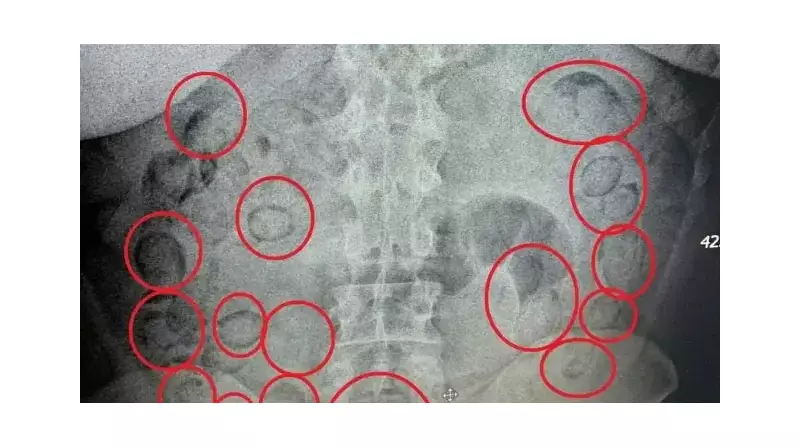

Şüpheli yakalandığında her şey normal görünüyordu ta ki hastaneye götürülüp röntgeni çekilene kadar. Görüntülerde midenin içinde onlarca küçük paket açıkça seçiliyordu. Doktorlar hemen müdahaleye başladı ve tek tek çıkarılan paketler sayılmaya başlandı. Sonuç inanılmazdı: tam 433 gram saf metamfetamin!

Bu yöntem aslında yeni değil -uyuşturucu kaçakçıları yıllardır 'body packing' denilen bu tekniği kullanıyor. Ama riski de bir hayli yüksek. Zira paketlerden biri midede yırtılsa, kişiyi dakikalar içinde ölüme götürebilir. Neyse ki bu sefer böyle bir trajedi yaşanmadı.